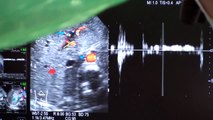

Conversamos con el periodista Francisco “Pancho” Saavedra, debió ser operado por problemas en su hígado. Era notorio el color amarillo de su piel y de sus ojos así que la alarma sonó. Hace más de un mes que sentía dolores y ya no pudo más. Un cálculo obstruía la vía biliar que impedía la baja de bilirrubina, además le provocó una inflamación del hígado que producía los dolores. Ayer, jueves 21 de agosto fue operado de forma ambulatoria.